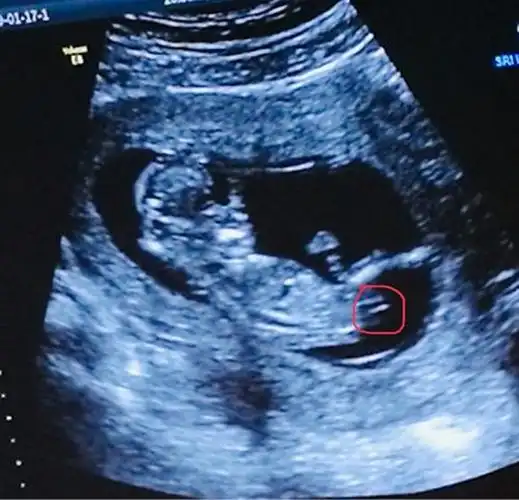

研究nub理论,nt图发来帮看男女,必回

nt怎么看男宝还是女宝 已生宝妈告诉你答案

nt图像上有三个点是怀女孩的概率更高吗?

坦然!nt检查值看男女的方法介绍"卓越成绩"-第1张图片-西卡博客